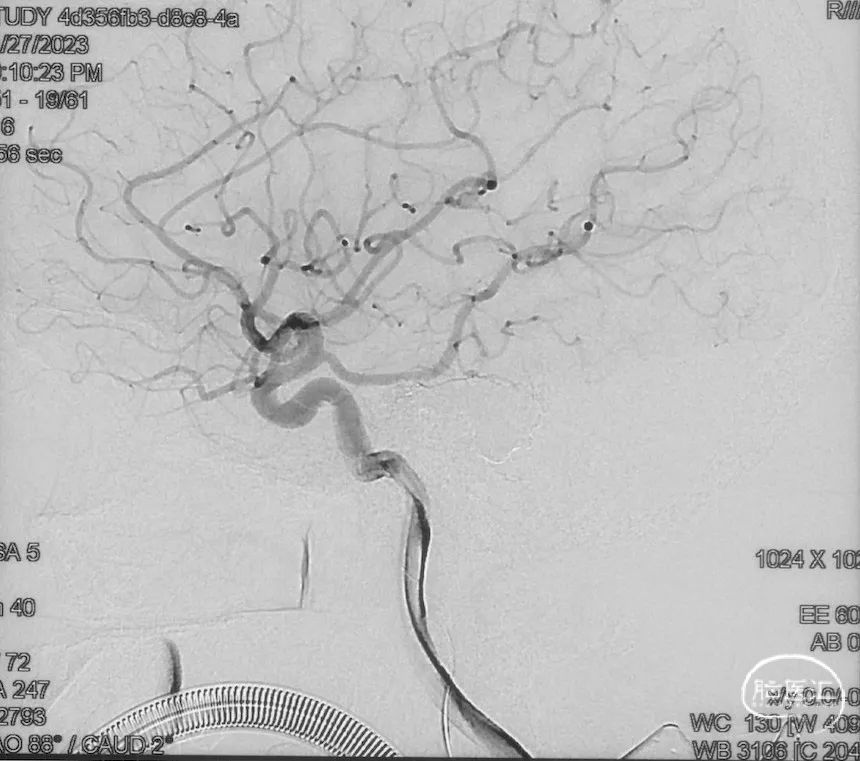

治疗结果

双侧颈外、颈内动脉正侧位造影瘘口均不显影

双侧椎动脉造影未见瘘口显影,可见广泛皮层静脉瘀滞

Onyx胶铸型显示瘘口形态。